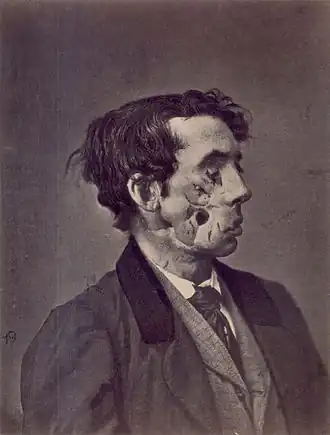

| Desenho de 1865 de um ferido na Guerra Civil Americana por conta de um bombardeamento. | |